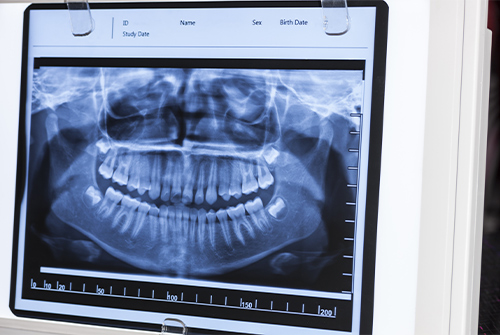

レントゲンは白と黒で画像が出されその中から虫歯なのかどうかを診査しています。金属は真っ白、プラスチックは少し黒くうつり、その間の色がセラミックと言われています。

そのため詰め物(インレー)の下の虫歯に関しては色の差異で虫歯を診断することができますが被せ物(クラウン)に関しては全てが白くうつってきてしまうため虫歯を発見するには至難の技です。

金属でもセラミックでも被せ物が入っている場合は痛みが出て、被せ物を外して虫歯が見つかるのがほとんどになります。